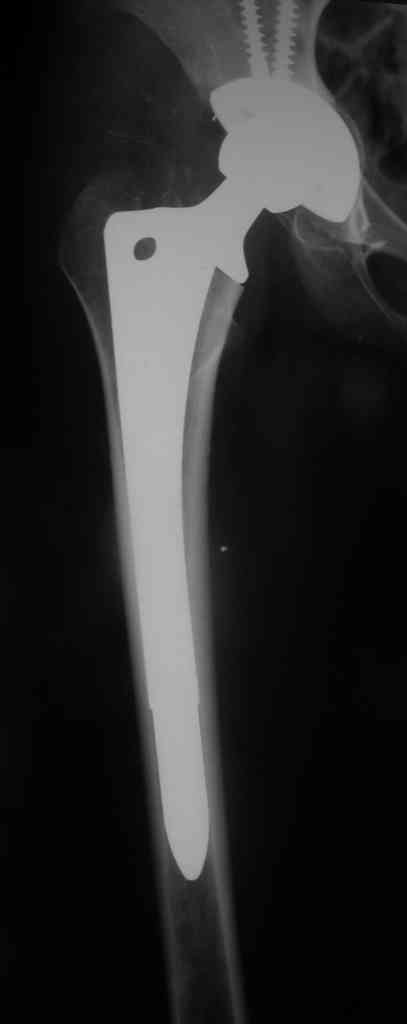

В июле 2004 года больной было выполнено тотальное эндопротезирование правого тазобедренного сустава бесцементным эндопротезом DePuy c ножкой AML. Послеоперационный период проходил гладко, исходом операции пациентка была довольна.

В июне 2006 года в ДТП была сбита автомобилем и получила поперечный оскольчатый околопротезный перелом в с/з диафиза бедра, с сохранением стабильности ножки протеза. Через 2 недели после травмы в клинике был произведен открытый остеосинтез бедра пластиной Bridge Plate DePuy. Больная ходила с костылями, через 3 месяца после остеосинтеза начала постепенно увеличивать нагрузку на ногу.

Через 6 месяцев клинически и на контрольных рентгенограммах было выявлена деформация бедра. Планируется провести реостеосинтез бедра аналогичной пластиной большей длины с применением костной аутопластики и (или) материалов типа MIIG, IGNITE, ALLOMATRIX.